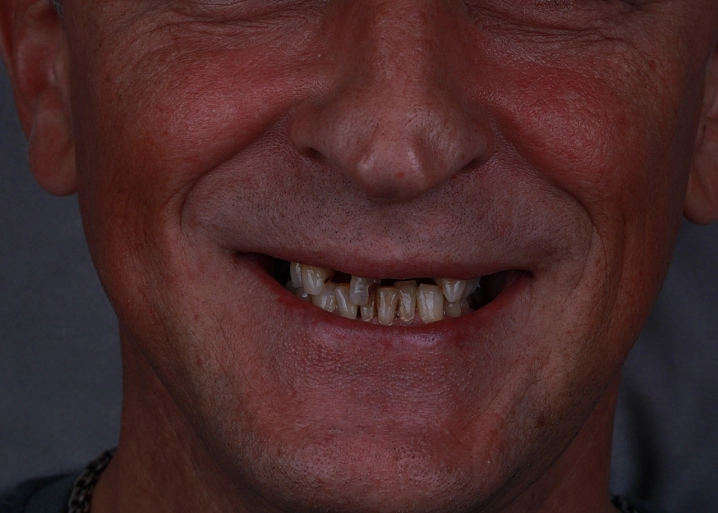

Циркониевый мостовидный протез представляет собой постоянную конструкцию, которая фиксируется на несколько опорных имплантов. Протез устанавливается после периода остеоинтеграции имплантатов через 3-6 месяцев. Коронки соединены между собой каркасом и представляют единое целое.

Существует 2 вида реставраций: с нанесением керамической массой и методом раскрашивания. Второй вариант в нашей клинике применяется чаще всего. Этот метод дает высокий эстетический результат. Первый вариант с нанесением керамики имеет недостаток, керамика может со временем скалываться, что вызывает неудобство в использовании протеза.